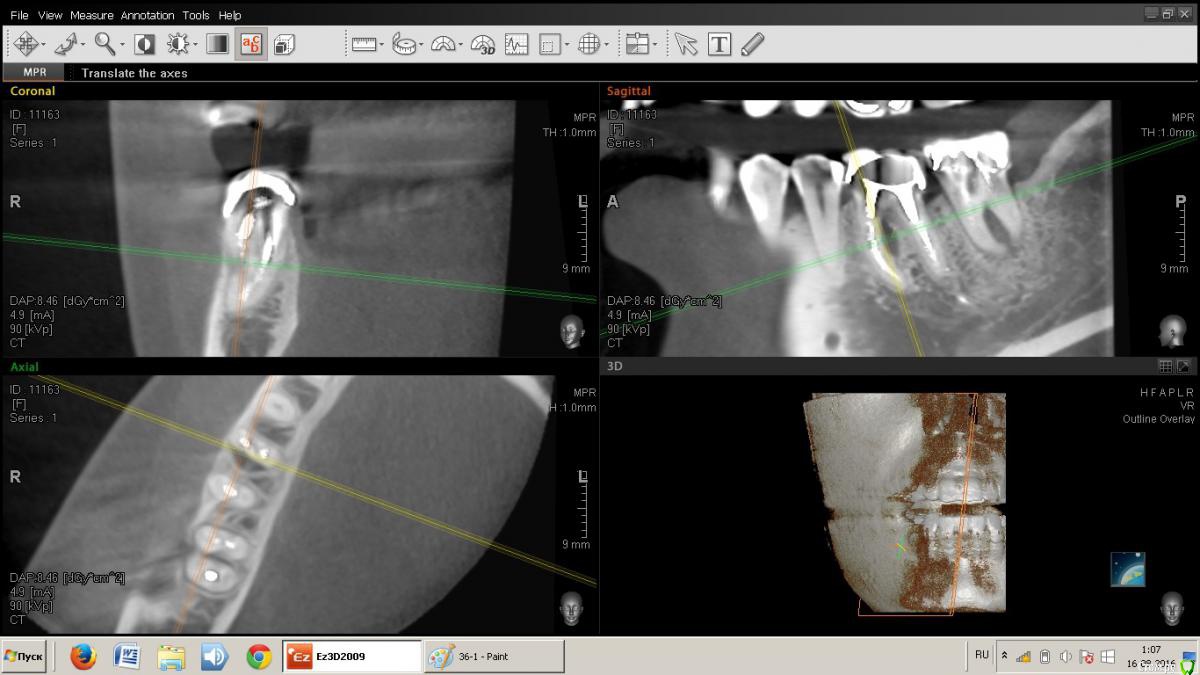

Kateryna Опубликовано 15 августа, 2016 Поделиться Опубликовано 15 августа, 2016 Добрый день, уважаемые доктора. Прошу совет. Уже смирилась с удалением семерки на нижней челюсти, трещина в корне, свищ. Сегодня была на консультации по поводу удаления и имплантации, врач рассматривая КТ сказал, что и шестой нужно удалять. Там инфекционный процесс. Чем поверг меня в глубокое "расстройство": операции, сумма в два раза больше чем я предполагала и т.д.Вопрос, действительно ли это необходимо, можно ли перелечить? Есть ли шанс?Ниже ссылка на КТ. https://yadi.sk/d/xhEvocCvu4RdN Ссылка на комментарий

DmitrySH Опубликовано 15 августа, 2016 Поделиться Опубликовано 15 августа, 2016 Здравствуйте, трещину седьмого зуба не увидел на кт, возможно в полости рта видно. На КТ он выглядит вполне нормально для попытки спасения.С шестым вот большой вопрос в сохранении, возможно нарушена целостность корня. Верхний шестой тоже обязательно лечить, вокруг корней тоже воспаление. Итого: то что видно на КТ. на трех зубах очаги воспаления. Трещин не видно ( их и не будет видно) Все три зуба можно попытаться вылечить, шансы 50/50. Ссылка на комментарий

колесников Опубликовано 15 августа, 2016 Поделиться Опубликовано 15 августа, 2016 Здравствуйте, трещину седьмого зуба не увидел на кт, возможно в полости рта видно. На КТ он выглядит вполне нормально для попытки спасения.С шестым вот большой вопрос в сохранении, возможно нарушена целостность корня. Верхний шестой тоже обязательно лечить, вокруг корней тоже воспаление. Итого: то что видно на КТ. на трех зубах очаги воспаления. Трещин не видно ( их и не будет видно) Все три зуба можно попытаться вылечить, шансы 50/50. По моему всё очевидно. 37 трещина по бифуркации,тотальная резорбция межкорневой перегородки и ограниченно -вестибулярной пластинки. 36 перфорация медиального корня в верхней трети с очаговой деструкцией в области межкорневой перегородки. Итого: 37 удаляется без вариантов. 36 удаление можно отсрочить на несколько месяцев ,но шансы на восстановление у него призрачны (перспективы перелечивания с закрытием перфорации в устье канала сомнительны,плюс остаётся нерешаемый очаг деструкции в перегородке) 2 Ссылка на комментарий

DmitrySH Опубликовано 16 августа, 2016 Поделиться Опубликовано 16 августа, 2016 По моему всё очевидно. 37 трещина по бифуркации,тотальная резорбция межкорневой перегородки и ограниченно -вестибулярной пластинки. 36 перфорация медиального корня в верхней трети с очаговой деструкцией в области межкорневой перегородки. Итого: 37 удаляется без вариантов. Если это трещина, то очень странная. Коллега, все может быть, но по КТ( не самого лучшего качества) выносить приговор зубу.. я пас. 36 удаление можно отсрочить на несколько месяцев ,но шансы на восстановление у него призрачны (перспективы перелечивания с закрытием перфорации в устье канала сомнительны,плюс остаётся нерешаемый очаг деструкции в перегородке) Не хочу переводить тему во флуд, но опять все боятся процессов в фуркации. 1 Ссылка на комментарий

колесников Опубликовано 16 августа, 2016 Поделиться Опубликовано 16 августа, 2016 (изменено) Есть проблема и у верхней шестёрки. Деструкция на верхушке медиального щёчного корня. Это лечится. Есть карман пародонтальный между 26 и 27. Это лечится. Но есть и подозрение на кариес корня . Этот вопрос решится только после снятия коронки. Изменено 16 августа, 2016 пользователем колесников Ссылка на комментарий